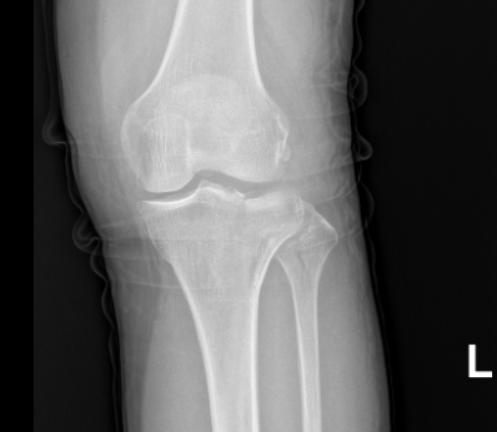

近日,何女士在家打扫卫生时不慎从高处摔下,自觉左膝部疼痛,不能站立行走,一开始她并未在意,认为休息几天慢慢会好,后来何女士见膝关节越来越肿胀并疼痛难以忍耐,在家人陪同下到我院拍片后示“左胫骨平台骨折”收入骨科一区治疗。

何女士的骨折情况属于上述第①条,经充分的术前准备后,张勇华主任为何女士行“关节镜下胫骨平台骨折复位内固定术”,手术仅切了3个小口,手术顺利,患者恢复非常好,术后3天就出院了。

术前关节面分离塌陷